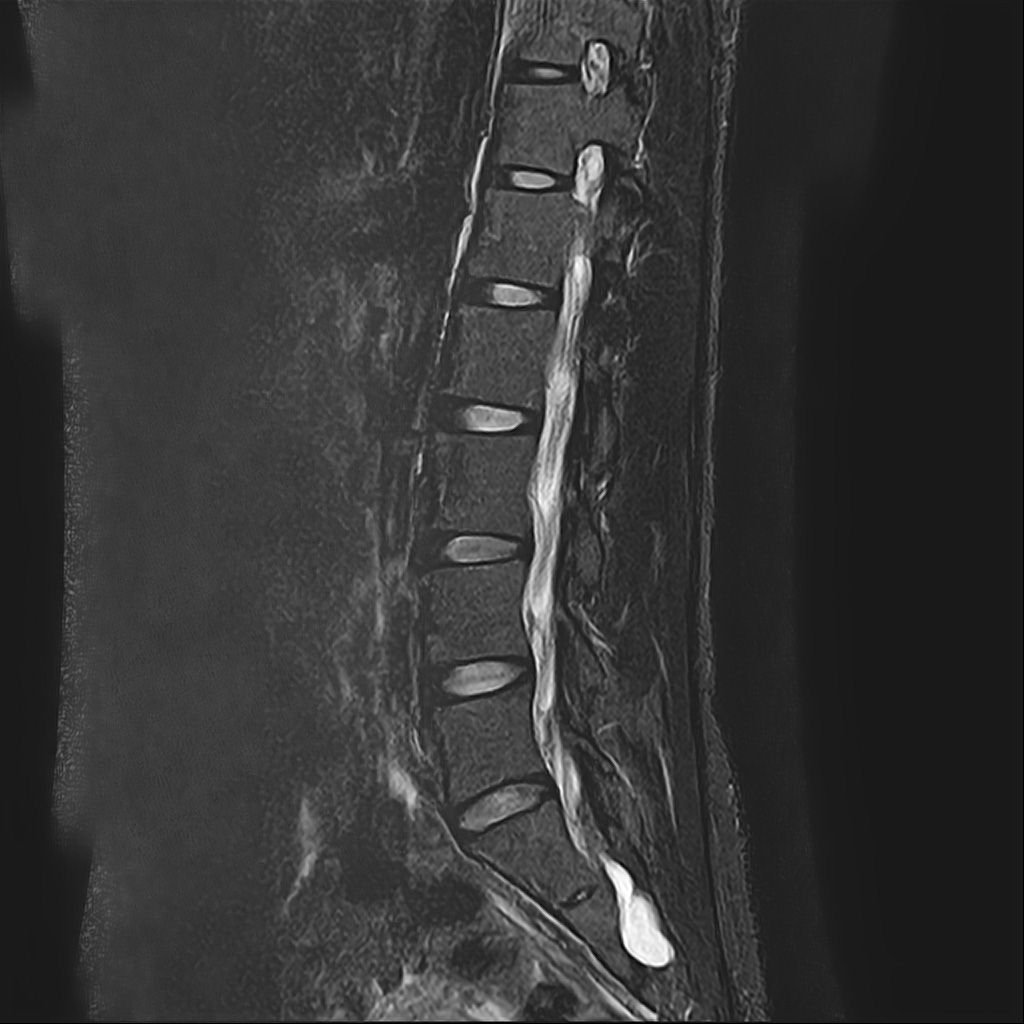

낭종s1-3번까지 꼬리뼈쪽으로 크게 나있다고했고, 단면상으로는 s2,3번이 촬영이 안되서 확인이안된다합니다. 허리디스크가 미약하게 4,5번에 있다고 했는데,

혹시 디스크로 인한 신경눌림인지, 낭종으로 인한건지 알수잇나요?